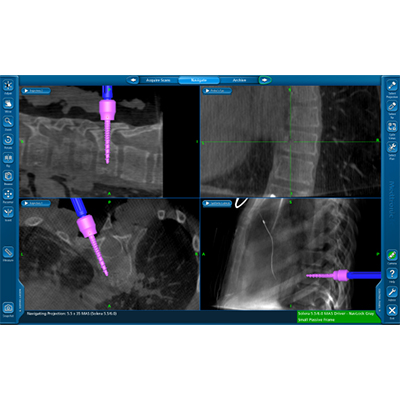

Επιπλέον, με τη χρήση της διεγχειρητικής τρισδιάστατης νευροπλοήγησης (ρομποτική χειρουργική της σπονδυλική στήλης), είναι εφικτή η ταχύτατη, με ακρίβεια και ασφάλεια, εμφύτευση των υλικών οστεοσύνθεσης και η πραγματοποίηση ακόμα και των πιο λεπτών χειρουργικών επεμβάσεων, σε όλες τις περιοχές της σπονδυλικής στήλης, από τον αυχένα έως και το ιερό οστούν. Η διόρθωση της παραμόρφωσης ελέγχεται διεγχειρητικά ενώ ο χειρουργός έχει τη δυνατότητα επιπλέον τροποποιήσεων την ώρα του χειρουργείου, ώστε να πετύχει το καλύτερο δυνατό αποτέλεσμα.

Διεγχειρητική τρισδιάστατη απεικόνιση σε πραγματικό χρόνο (ρομποτική χειρουργική), για την ασφαλή και ακριβή τοποθέτηση των χειρουργικών υλικών σπονδυλοδεσίας (α), αντιμετώπισης όγκου στον αυχένα - σπονδυλοσπλαστική (β, γ), και οστικής μετάστασης στη λεκάνη - θερμική εκτομή του όγκου με ραδιοσυχνότητες(δ)